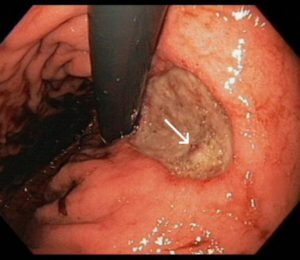

Можливо, лікар порекомендує обстежити кишечник за допомогою колоноскопа. Метод допоможе виявити новоутворення в органі та ступінь їх розвитку. Також при колоноскопії допустимо взяти матеріал на гістологічне дослідження прямо під час процедури.